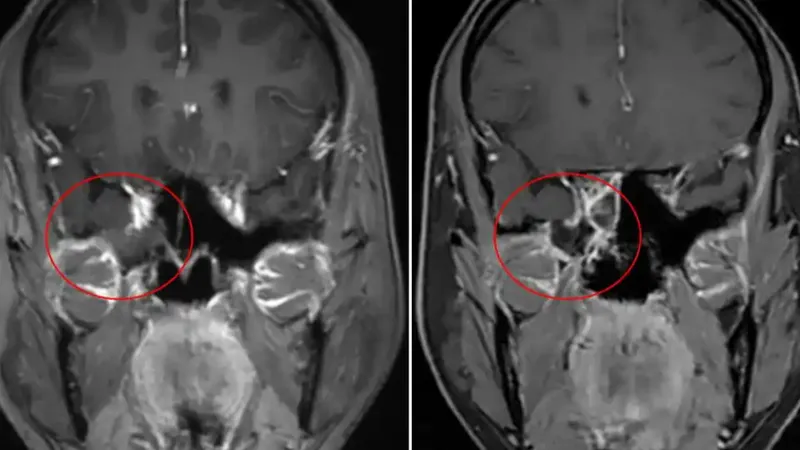

春夏交替之际,鼻炎、呼吸道感染等疾病多发,广东39岁居民罗女士因此没将自己反复流涕的情况太当回事,直到20天后她在耳鼻咽喉头颈外科确诊患上脑脊液鼻漏。专家提醒,脑脊液鼻漏可导致颅内感染风险、颅内低压、脑膜脑���出等严重危害,一旦确诊,应尽早手术。